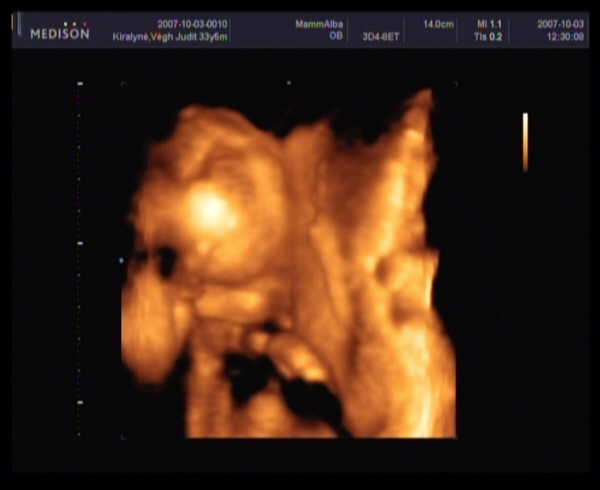

Megjöttem a 4D-ről.

Szupi volt, bár sajna kicsi bogaram állandóan vagy a néhlepénybe furta az arcát, vagy a kezecskéit tette az arcocskája elé, és elég nehéz volt rendesen elkapni.

Amugy minden rendben van, 20 hetesnek megfelelő.

BPD - 4,97 CM

HC - 18,18 cm (ez nem tudom mi, de ez alapján 20+3 hetes)

FL - 3,10 CM

Átlagos magzatvíz, normális placenta, eltérés nem látható.

És végre a lábaközét is megmutatta nekünk.

Ha jól látom az első képet, (nem biztos) akkor PÖCSÖS!!!!!!!!!

Szerintem kislány!Én látom a szoknyáját :lol: :lol: :lol: :lol: